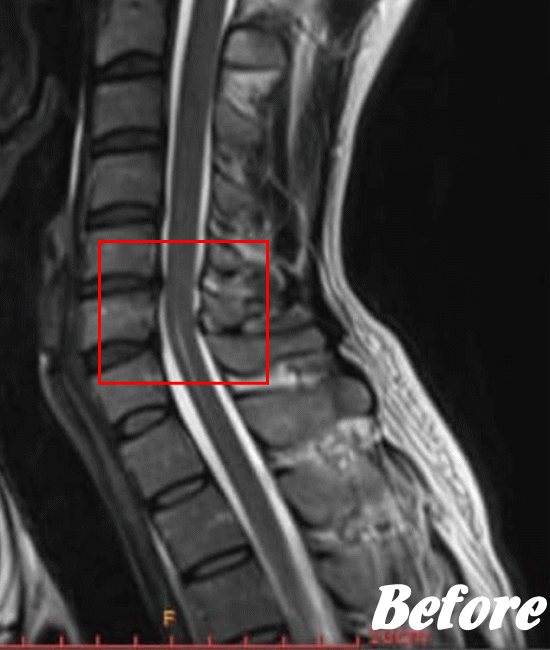

・指の変形

レントゲン撮影やCT、MRIなどにより診断します。頚椎症と診断されると、主に以下の治療が行われます。基本的には、保存療法がおこなわれます。

HALOカイロプラクティック☆平和島整体院では、骨盤から背骨全体(腰椎、胸椎、頸椎)を調整し、肩甲骨の動きを柔軟にし、首周りの筋肉をゆるめ、頚椎の骨と骨との間隔を広げ、動きを滑らかにして、首の負担を軽減させながらバランスを整える施術を行います。

頚椎症は、速効矯正・即効施術の【体の整体】の適応になります。